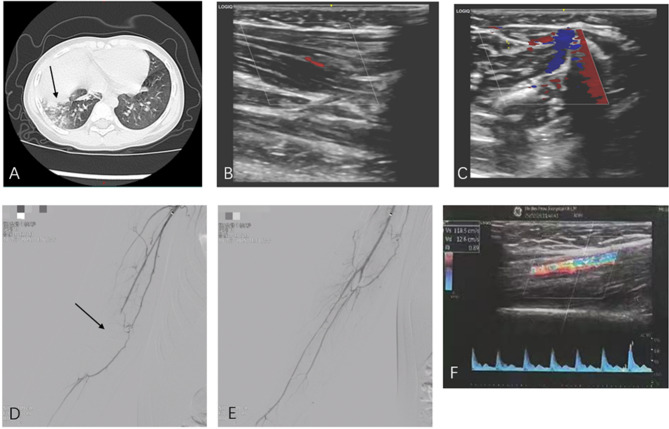

Background: Mycoplasma pneumoniae pneumonia complicated with arterial embolism in children is rare but progresses rapidly, potentially leading to severe limb ischemia and disability. This study reports a case of MPP complicated with upper limb arterial embolism and reviews relevant literature to explore its pathogenesis, treatment strategies, and clinical management principles.

Case presentation: On January 9, 2025, Hebei Provincial Hospital of Traditional Chinese Medicine admitted an Asian male pediatric patient with upper limb arterial embolism. The patient developed acute limb ischemia secondary to Mycoplasma pneumoniae pneumonia and was diagnosed with upper limb arterial embolism. Endovascular thrombectomy was performed, followed by postoperative anticoagulation, anti-infective therapy, and traditional Chinese medicine treatment. After comprehensive management, the ischemic condition of the affected limb significantly improved, with no obvious functional impairment, achieving satisfactory therapeutic outcomes.